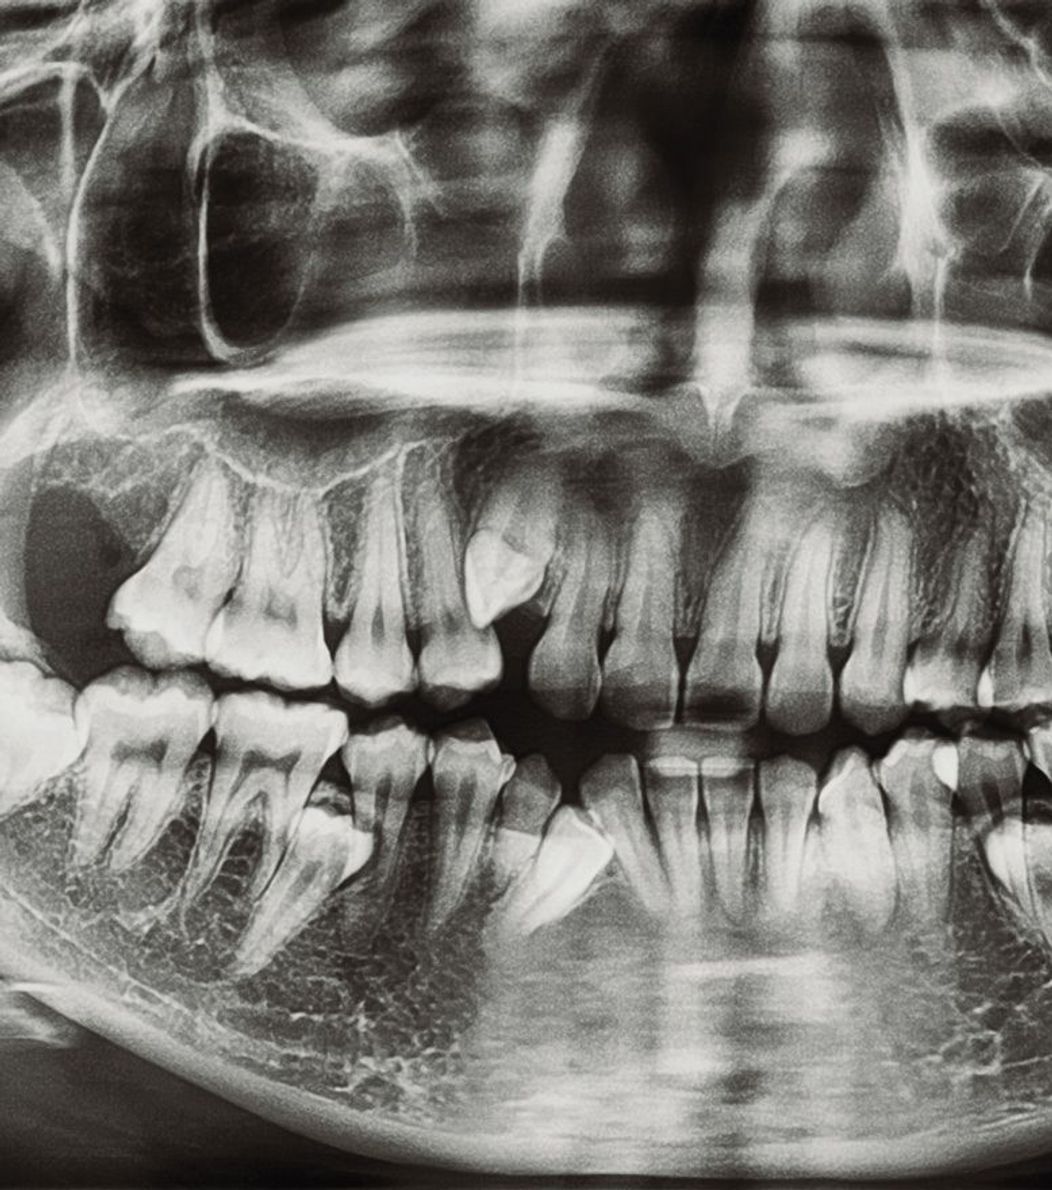

When you have severe tooth pain, it can be a real dental emergency—and Nu Dentistry is here to help you through them all, including teeth extraction. While it may sound scary, our friendly, gentle dentists make sure you’re always relaxed in our office. There are 2 main types of tooth removal procedures: Simple extraction. A simple extraction is used to remove teeth that are visible. Once local anesthetic has properly numbed the area, your dentist will use a tool called an elevator to loosen your tooth and forceps to fully remove it from your gum. Surgical extraction. A surgical extraction is instead performed on teeth that are not visible, like fully submerged teeth or teeth that have broken off below the gum-line. Our on-site oral surgeon will make an incision and extract your tooth directly from your gums. Since this method is more intensive, the surgeon will most likely give you a mix of local anesthetic and sedation, including oral or IV sedation. This ensures both your body and mind are relaxed and comfortable throughout your treatment. After your treatment, we’ll prepare you with aftercare instructions to ensure that your mouth stays healthy and heals quickly without any complications. Within a week or two of your procedure, new bone and gum tissue will fill the gap your tooth left behind. At Nu Dentistry, we understand that you can’t always plan when you have a toothache or when your molars are coming in. That’s why if you need emergency tooth extraction, we’re on-call and ready for you. We do our best to ensure you’re in our patient suites within minutes of your arrival. If you need to call our on-site staff to schedule an immediate appointment, call us now at +18329164144.